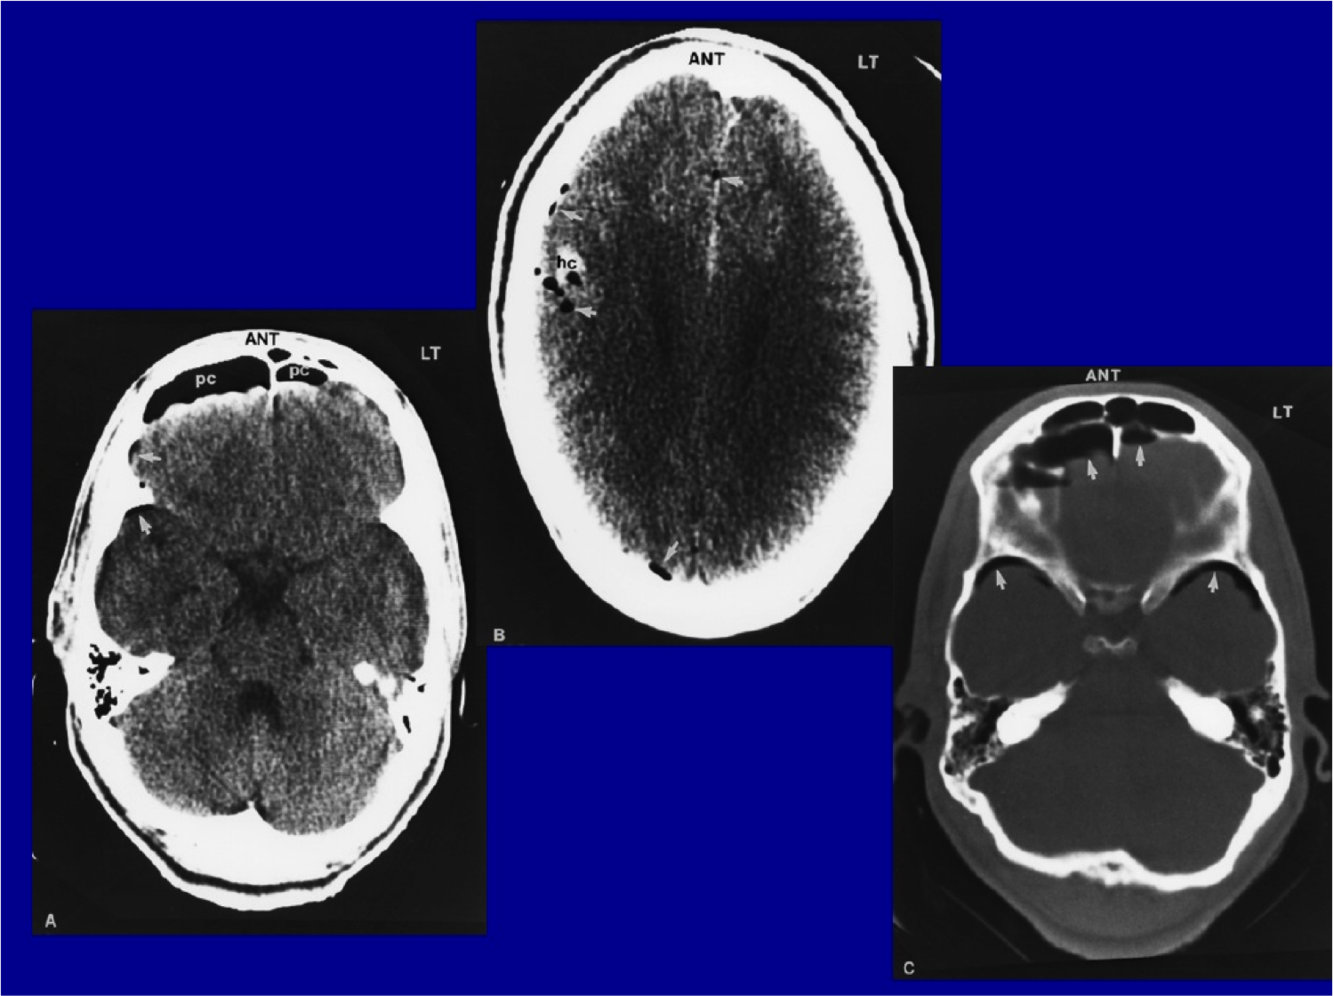

What is shown

pneumocephalus (probably fracture in sinuses or mastoid where there is air)

WHat do you see?

Diffuse cerebral edema